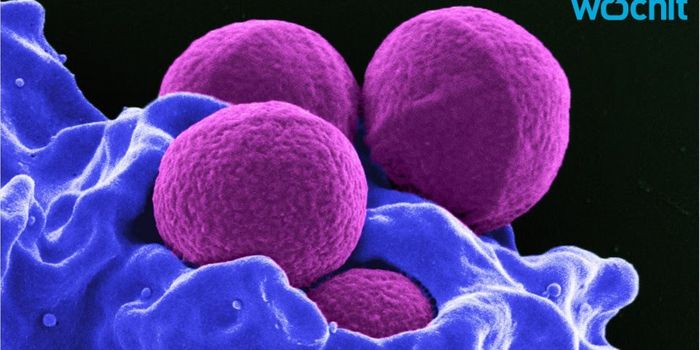

NOV 01, 2017VideosCells in the body have developed a variety of strategies toward removing harmful bacteria from the body. Phagocytosis is ...